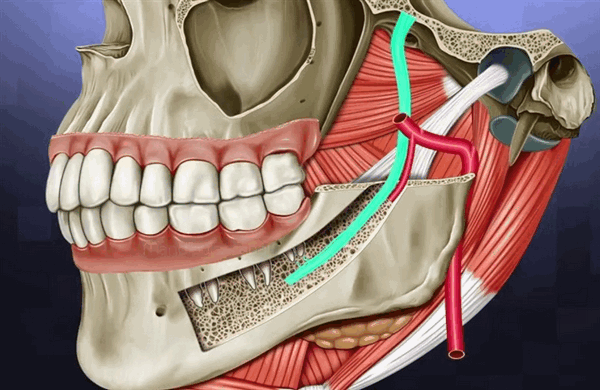

Нижняя челюсть

Перед операцией определяют положение нижнечелюстного канала и лицевой вены. Травма вены может привести к повреждению сосудисто-нервного пучка, как следствие, к кровотечению и отеку. Повреждение альвеолярного нерва приведет к потере чувствительности (парестезия).

Во время процедуры аккуратно отслаивают десневой лоскут, не используют режущие инструменты вокруг нервов, препарирование прекращают за 2 мм до нерва.

Оценивается расположение, длина, наклон зубных единиц в месте планируемого ложа. Важно сделать прицельный снимок, чтобы определить направляющую ось и угол наклона стержня.

Если не сделать снимок повышается риск нарушения расстояния между стержнем и единицей. Это может привести к травме корня, периапикальных тканей, вплоть до потери зуба.